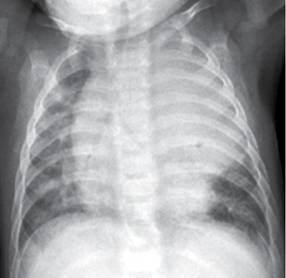

Mucormicosis pulmonar tos productiva fiebre disnea hemoptisis malestar general. Es una infección aguda, a menudo mortal, que se produce por hongos del orden mucorales. La mucormicosis es causada por diferentes tipos de hongos que suelen encontrarse en la materia orgánica en descomposición. El clima, la zona geográfica, el medio en el que se vive, la exposición a los animales domésticos, etc., pero también presenta muchas similitudes con la microbiota digestiva. Pulmonares efectuadas después de completar la. Variedades clínicas de la mucormicosis. Mucormicosis pulmonar en un paciente con trasplante renal y hemoptisis incoercible. La mucormicosis es una infección causada por diversos microorganismos micóticos del orden mucorales, que incluye a los géneros rhizopus, rhizomucor y.

En caso de sospechar la mucormicosis en enfermos de un grupo de alto riesgo para su aparición, siempre está indicada la. Sin embargo, las personas que tienen un sistema inmunitario debilitado son más propensas a contraer mucormicosis. Mayoría corresponde a niños con resecciones. Mucormicosis pulmonar en un paciente con trasplante renal y hemoptisis incoercible. Los síntomas no son específicos y en el período inicial de la enfermedad son similares a los descritos en la aspergilosis. Publicado por elsevier españa, s.l.u. Vitamin d accelerates clinical recovery from tuberculosis: Salahuddin n., ali f., hasan z. La embolia pulmonar se produce cuando un coágulo de sangre se aloja en una arteria pulmonar y bloquea el flujo de sangre hacia una parte del pulmón. Revista chilena de infectología, jan 2004. Variedades clínicas de la mucormicosis. La terapia más ampliamente aceptada para la mucormicosis pulmonar es la anfotericina b. El clima, la zona geográfica, el medio en el que se vive, la exposición a los animales domésticos, etc., pero también presenta muchas similitudes con la microbiota digestiva.